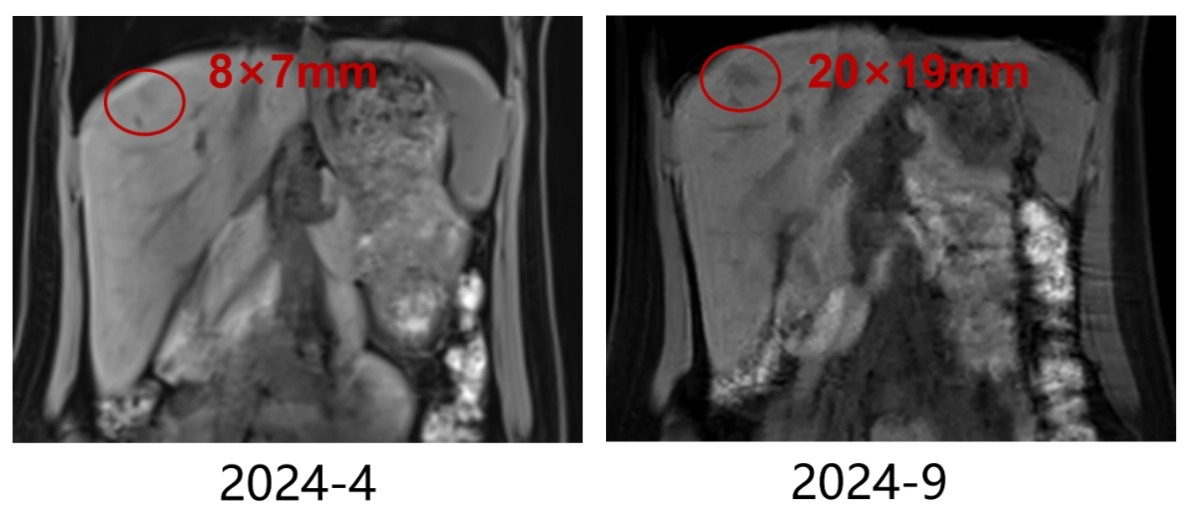

疗效评估:疾病进展(PD),PFS仅2个月,考虑原发性内分泌治疗耐药。

上腹部MR(2024-9)肝脏多发转移瘤,数量较前增多,S2、S4、S5部分结节较前增大,S4包膜下结节较前稍缩小,S6结节同前相仿。

0926-03.png

疗效评价:肝脏病灶明显缩小,最佳疗效PR,PFS>11个月。

肝脏转移瘤(较大者)缩小情况

0926-04.png